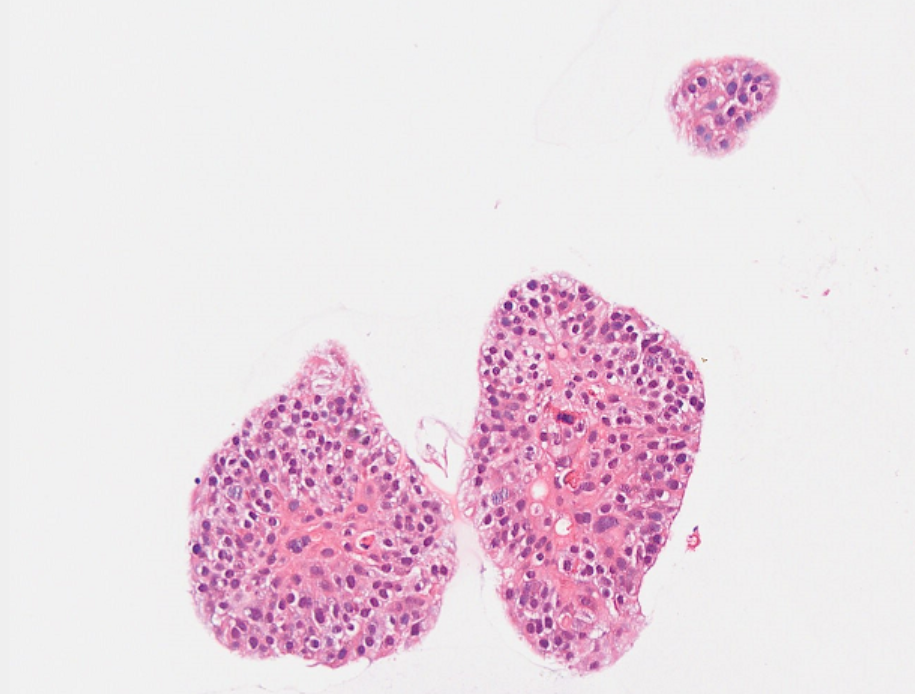

IV. Organoid Identification - HE Staining Results (with Lung Cancer as an Example)